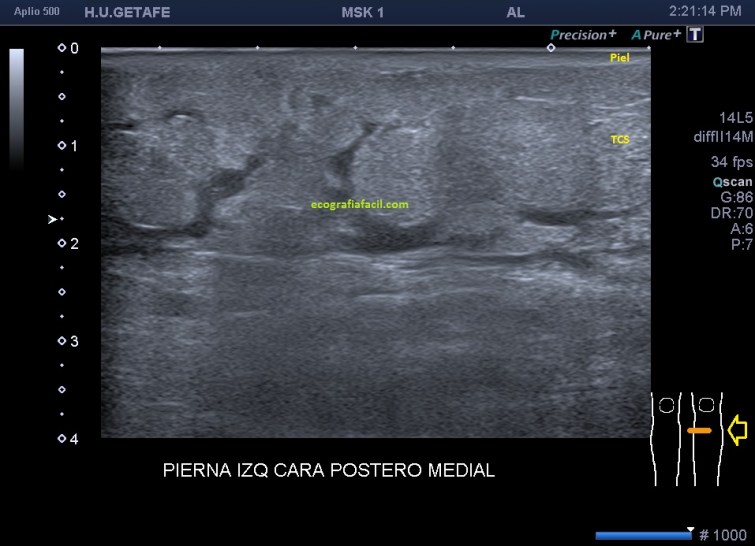

Lo que me encontré al colocar el transductor es esta imagen que ves, la imagen 1:

Después de estudiar la zona a conciencia, en ambos planos, lo que se objetiva es una cambio en la región de la piel y el TCS, la piel se muestra engrosada, ha perdido su homogénea linealidad hiperecogénica y se observa hipoecogénica y heterogénea, debajo de ella, el TCS que tiene un aspecto de nubes con zona hipoecogénicas que las rodean, que es líquido entre la grasa.

Estos cambios tienen que ver con edema de partes blandas. Buscando la extensión de estos cambios recorrí la pierna izquierda hasta la rodilla, observando cambios en todo el recorrido, estando en el tercio medio y proximal del miembro, la piel algo más conservada, y el TCS hiperecogénico aunque parece que con algo menos de líquido entre la grasa, como muy bien puedes observar en la imagen 3.

3